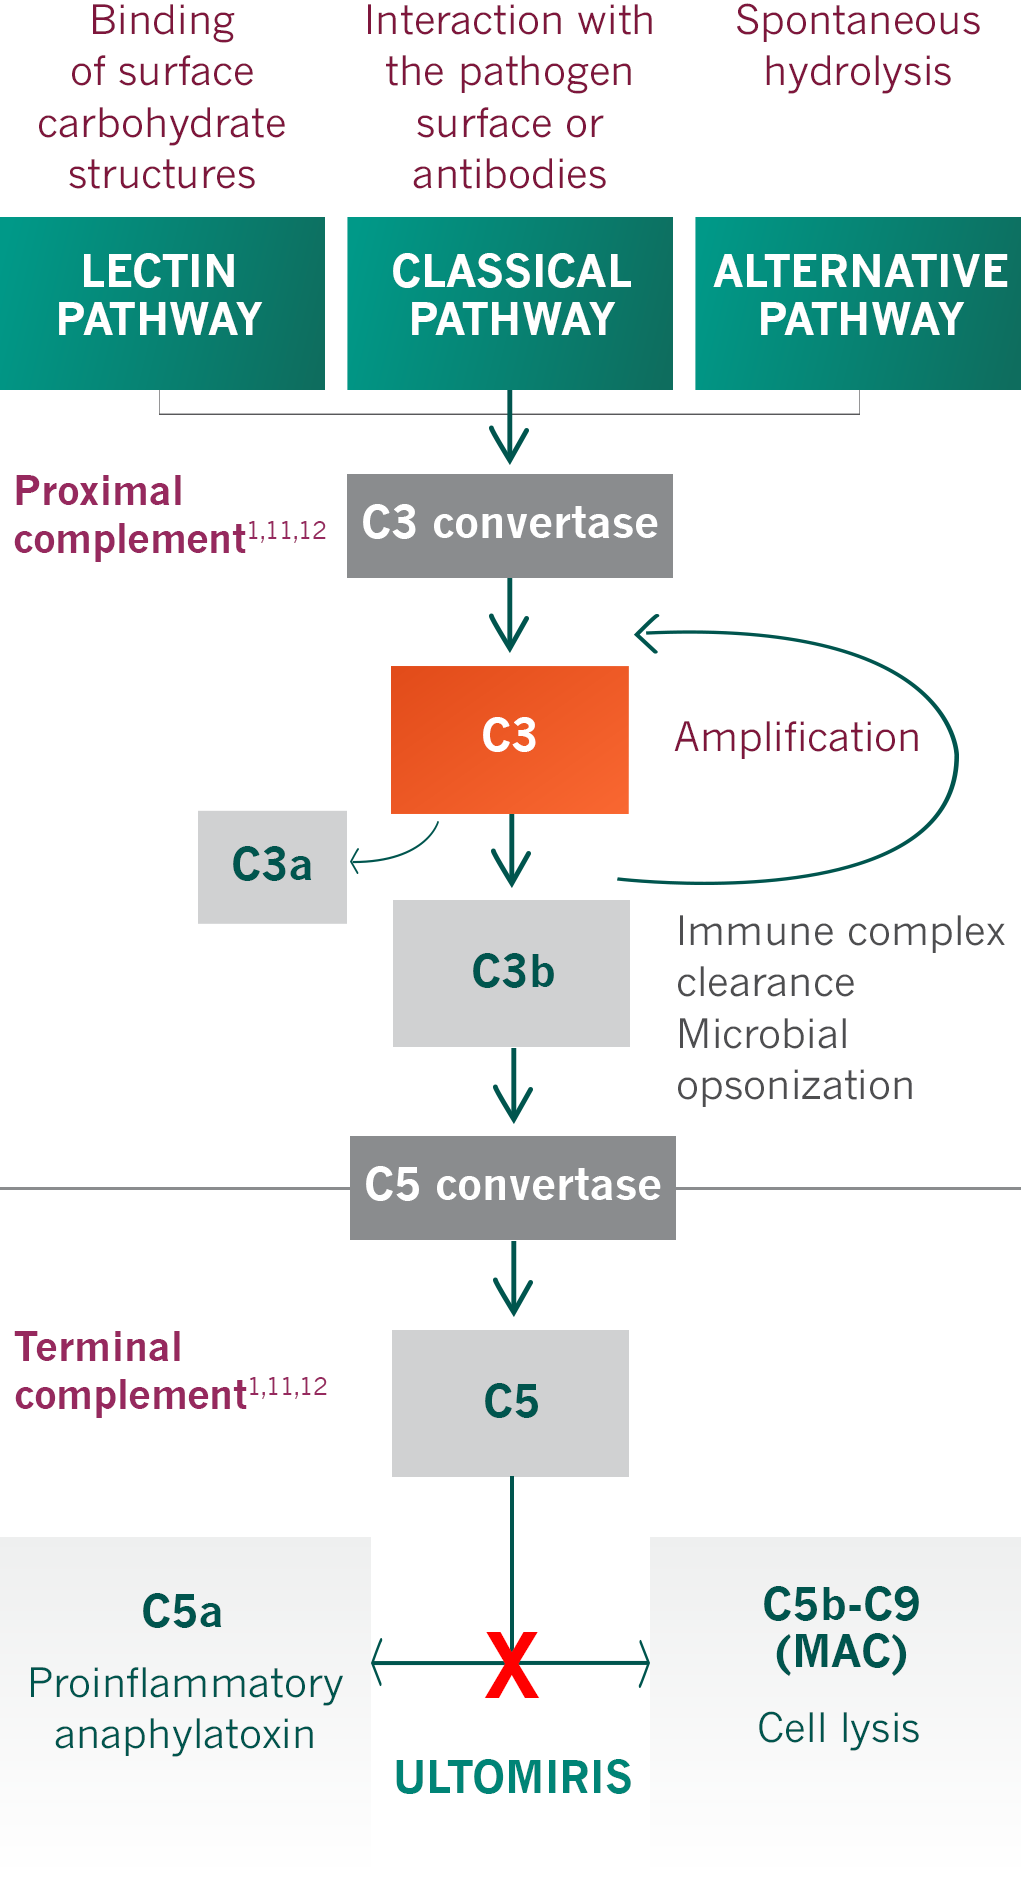

ULTOMIRIS, a complement inhibitor, increases a patient’s susceptibility to serious, life-threatening, or fatal infections caused by meningococcal bacteria (septicemia and/or meningitis) in any serogroup, including non-groupable strains. Life-threatening and fatal meningococcal infections have occurred in both vaccinated and unvaccinated patients treated with complement inhibitors.

ULTOMIRIS blocks terminal complement activation; therefore, patients may have increased susceptibility to infections, especially with encapsulated bacteria, such as infections caused by Neisseria meningitidis but also Streptococcus pneumoniae, Haemophilus influenzae, and to a lesser extent, Neisseria gonorrhoeae. Patients receiving ULTOMIRIS are at increased risk for infections due to these organisms, even if they develop antibodies following vaccination.